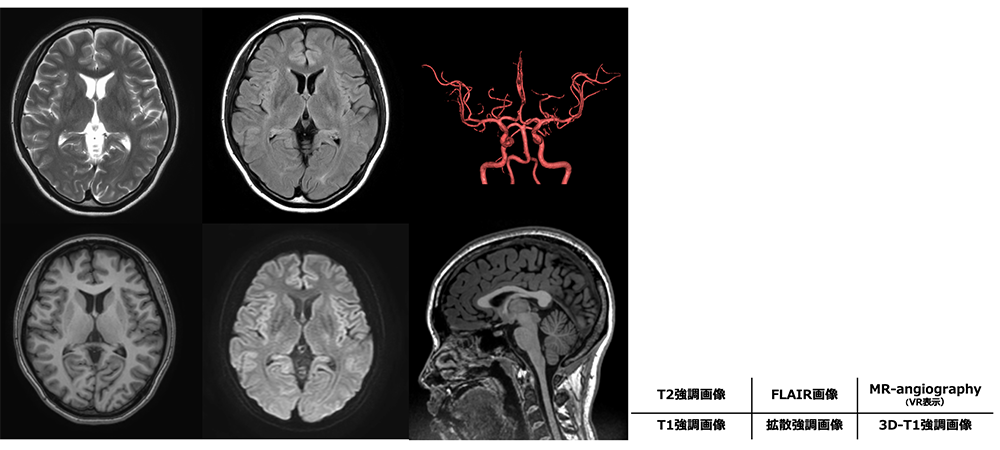

頭部MRIは脳の正常組織と病変部のコントラストを明瞭に描出できるため、疾患の有無を診断するのに有用です。また、 MR angiographyは造影剤を用いることなく脳血管を描出することができるため、血管の狭窄や動脈瘤の発見に役立ちます。